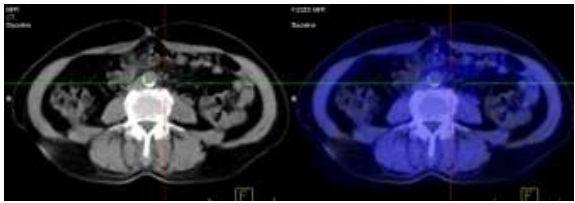

- Chụp PET/CT:

Hình 1.1. Khối đại tràng phải, kích thước: 3x4cm, SUV=7,9.

Hình 1.2.Hạch ổ bụng đường kính: 0,6cm, SUV=2,9.

Hình 2.1. Hình ảnh PET/CT trước điều trị: có khối u đại tràng phải tăng hấp thu FDG.

Hình 2.2. Sau 6 chu kỳ hóa trị: Không thấy hình ảnh khối u đại tràng phải tăng hấp thu FDG.

Hình 2.3. Sau 6 chu kỳ hóa trị: Không thấy hình ảnh hạch ổ bụng tăng hấp thu FDG